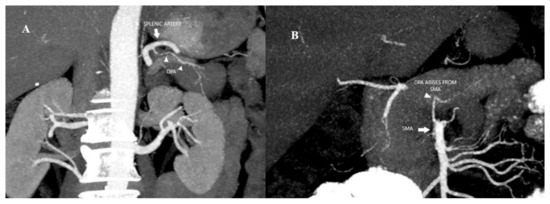

| The DPA Variations | |||||||

|---|---|---|---|---|---|---|---|

| SA | CHA | GD | SMA | CELIAK | DUAL | p Value * | |

| Frequency n (%) | 110 (69.2%) | 7 (4.4%) | 6 (3.8%) | 28 (17.6%) | 6 (3.8%) | 2 (1.2%) | |